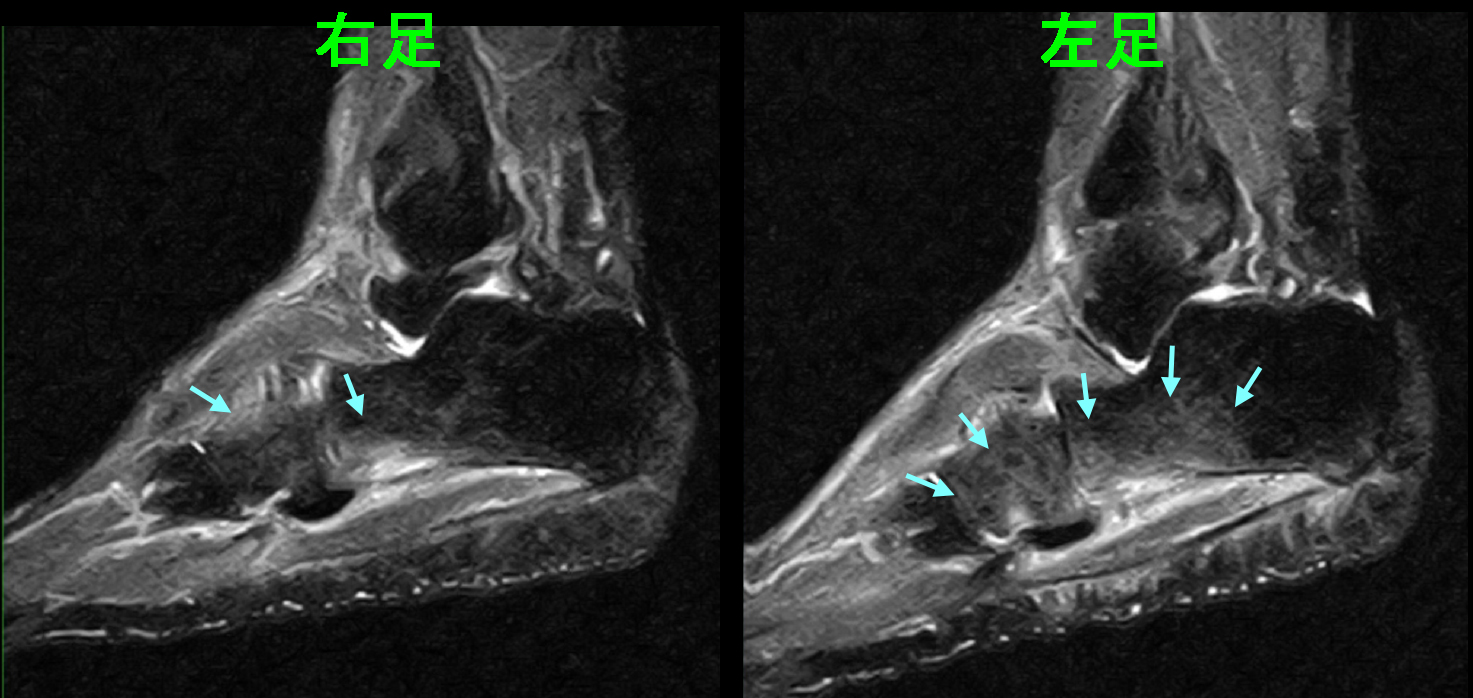

31才男 初診時MR3.jpgこのMRI画像では、両側のかかとの骨(踵骨)が白くなっており、骨の炎症の所見です。(青矢印)